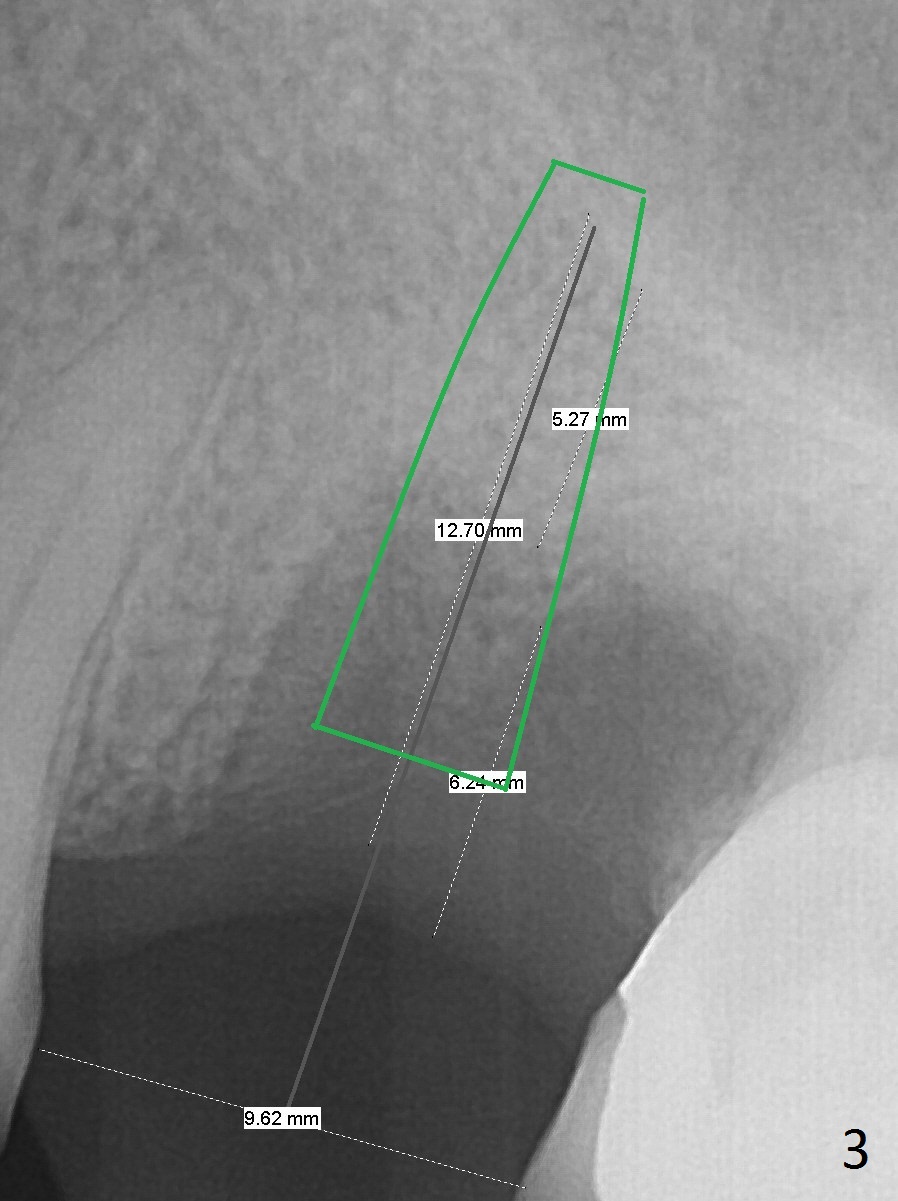

Low Density Post Extraction

A 44-year-old woman will return to clinic for #14 implant placement 2.5 months post extraction (Fig.1). The tooth used to have persistent fistula. The bone density appears to be low coronally. To compensate for the sloped sinus floor (arrowheads), start osteotomy as mesial as possible (Fig.2 red arrow) either with Magic Expander or Drill and place an implant as high as possible (Fig.3). If there is buccal plate defect, place the implant as palatal and deep as possible. Use Metronidazole routinely for sinus cases.